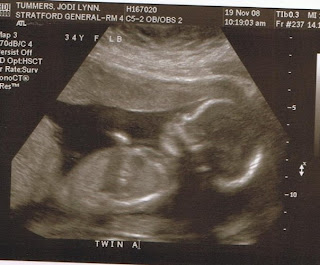

These little boys changed my life forever.  From the moment I learned I was pregnant with not just one surprise baby but two my life has been forever changed, forever blessed.

I could spend days remembering on here...the feelings I had when I learned, the ways I shared that with everyone, the varying emotions I felt in those first few weeks.  I could share all the plans I had, the joy I felt at each ultrasound, the excitement I had as I organized bedrooms, arranged to get two of everything, ordered and received my HUGE double stroller.

And of course I could spend a long time remembering that fateful day....the long wait in the ultrasound room, the face of my doctor as he shared the diagnosis, the trip to Toronto, the official diagnosis and treatment plan, the surgery and then, of course, the horrible news.